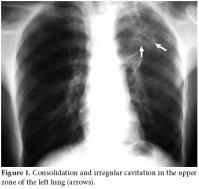

Consolidation and irregular cavitation in the upper zone of the left lung was detected in the chest radiograph (Figure 1); however, knee radiographs were considered normal. Magnetic resonance imaging of the right knee revealed inflammation in the knee, around the joint and in the superior tibiofibular articulation. The knee MRI also revealed centrally necrotic abscesses with peripheral enhancement of the rim after a gadolinium injection (Figure 2). An MRI of the right shoulder also showed increased inflammatory signal changes in the acromioclavicular joint and adjacent soft tissue with enhancement after gadolinium injection (Figure 3). The purified protein derivative (PPD) skin test for Tbc measured 22 mm. A synovial biopsy taken from the knee detected granulomatous inflammation with caseation necrosis. Antibiotic treatment with isoniazid, rifampicin, ethambutol and pyrazinamide were prescribed for two months followed by rifampicin and isoniazid for seven months. The patient showed significant improvement in the knee and shoulder within two months and close to complete improvement within six months.

Magnetic resonance imaging is the best modality to evaluate soft tissue affection by demonstrating marrow changes, joint effusion, synovitis, pannus, and cartilage and bone erosions.[2,16] Joint and periarticular involvement and lesions are particularly well defined by an MRI. The definitive diagnosis is performed from a positive mycobacterial culture and a histological examination of synovial fluid or synovial membranes. An examination of a biopsy specimen is an important and useful diagnostic method. Amplifying DNA of Mycobacterium tuberculosis from synovial fluid or bone by PCR could be useful for the early diagnosis of Tbc. We performed a definitive diagnosis through the histopathological examination of a synovial biopsy, a chest radiograph showing cavitation and the definitive demonstration on MRI examination. This was done in spite of the lack of positivity of mycobacterial culture and PCR. In addition, following the initiation of specific antituberculous treatment, the patient showed significant improvement in the knee and shoulder within two months with close to complete improvement within six months. We extended treatment to nine months in accordance with the recommendations for musculoskeletal tuberculosis in the literature and by the Turkey Ministry of Health.[17,18]